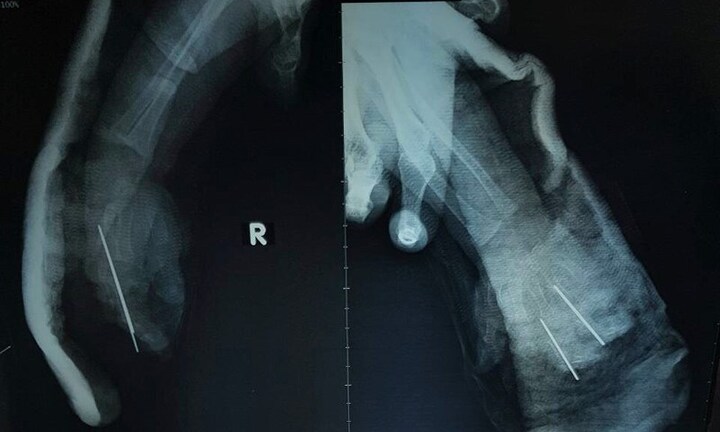

Ngay sau đó, bé được đưa đến bệnh viện Nhi Trung ương trong tình trạng một bên bàn tay phải bị đứt gần rời, chỉ còn phần da dập nát.

Để phục hồi bàn tay cho bé, các bác sĩ đã tiến hành kết hợp xương, nối lại bó mạch quay, bó mạch trụ, thần kinh giữa và nối lại hệ thống gân gấp và gân duỗi, tĩnh mạch nông. Đây là một kỹ thuật phức tạp do hệ thống mạch, thần kinh, gân cơ ở bàn tay của trẻ đều nhỏ và bị máy cán dập nát.

Ca phẫu thuật kéo dài sau 6 tiếng đã có kết quả thành công. Được biết, ngay sau ca phẫu thuật tay phải của bệnh nhi đã hồng ấm.

Sau mổ 5 ngày bé đã có thể nhúc nhích các ngón tay. Tuy nhiên, để bàn tay hoạt động tốt cháu bé cần trải qua một khoảng thời gian tập phục hồi chức năng nữa.